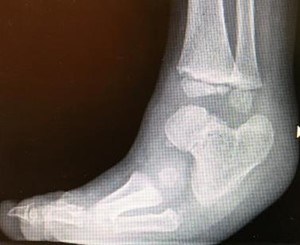

In fibular hemimelia, the fibula is hypoplastic (short, poorly developed) or completely absent. This is associated with varying degrees of alterations of the tibia, knee, ankle, and foot, and a shortening of the leg segment.

Ankle deformity

In fibular hemimelia, the ankle can be affected in a very variable manner, from no changes to mild valgus to severe articular alteration. Consequently, the joint can present as stable or unstable and deformed in equinus, varus, or valgus (see Paley classification below).

Part of the problem stems from the lack of the normal stabilizing function of the distal part of the fibula (lateral malleolus). Without this, the ankle will tend to show instability or outward subluxation.

Part of the problem, however, stems from the articulation between the talus and the calcaneus (subtalar), which is often malformed or fused , and this fusion may be present in an altered direction.

Foot deformity

In fibular hemimelia, the foot can be affected to varying degrees. The lateral aspect of the foot is usually primarily affected, precisely because the initial pathological process (during pregnancy) affects the lateral development of the leg (fibula) and foot.

This frequently results in the absence of the toes and lateral metatarsals, to varying degrees (four-toed foot, three-toed foot, etc.).

Tibial deformity

Fibular hypoplasia is often associated with a deformity of the tibia at the diaphysis level, with a tendency toward valgus and procurvation.

A typical skin umbilication is often present at the apex of the deformity , but this has no pathological significance.